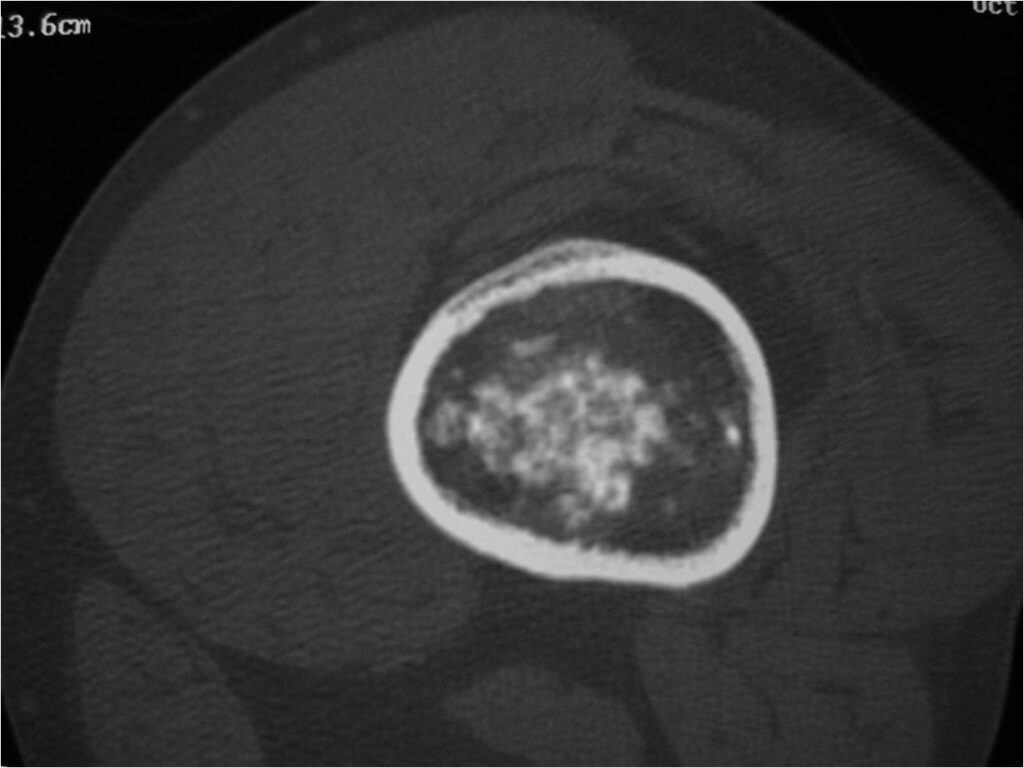

- Localized, radiolucent defect usually with punctate calcifications

- Calcifications are stippled, punctate, popcorn like calcifications and “Ring and Arc” calcifications

- Chondroid matrix with calcifications in majority of tumors

- MRI

- Lobulated margin

- Marked increased intensity long TR images

- Calcified chondroid – low intensity all sequences

- Lobulated margin (Lobular Growth Pattern)

- T2 Weighted Images: High Signal Intensity

- High water content shows as high signal on T2 weighted images

- Calcifications will be low signal